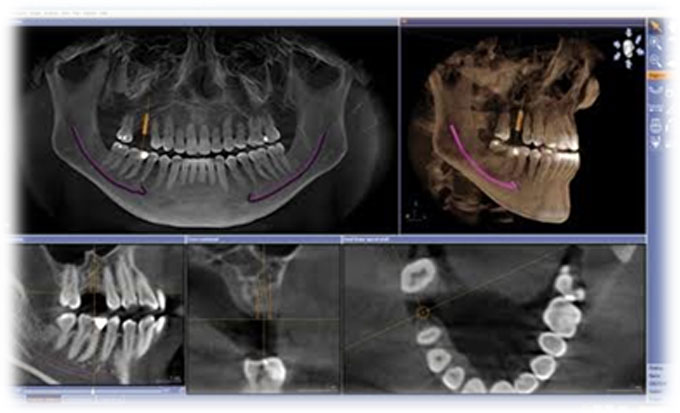

Guided Implant Surgery involves the use of advanced 3D imaging and computer-aided design (CAD) to plan the exact placement of dental implants. This meticulous planning process allows our dental specialists to visualize the patient’s oral anatomy in great detail, ensuring the implants are placed in the most ideal position for both functionality and aesthetics. The procedure is tailored to each patient's unique needs, ensuring a personalized treatment plan.

These technique assures that the implant is precisely placed without any damage to nerves, vessels and wouldn't perforate maxillary sinus too.